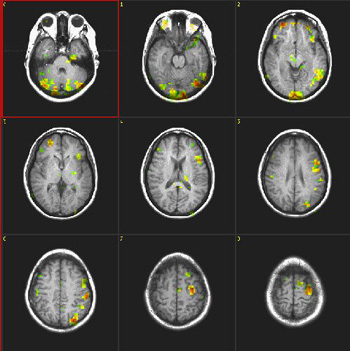

| Subject | Right handed 34 year-old-woman. Native language: Spanish | ||||||

| Paradigm | Type: Verbal fluency task ON: Retrieve verbs related to presented nouns OFF Spell given words | ||||||

| Statistics |

| Images |

| Activation | There is activation of Broca's area in both languages. The right thalamic activation is noted only in the second language. There is also greater activation of the right inferior frontal gyrus in the second language than in the mother language. SMA is more pronounced on the right in both languages. |